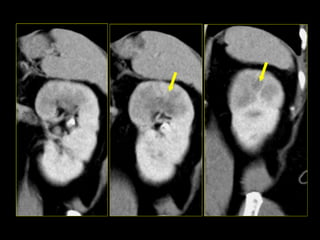

Caso # 9 ♀ , 35 años, con sospecha de proceso apendicular retrocecal por lo que se solicitó TC abdominal. Se realiza estudio en cortes axiales, se muestra la fase arterial, venosa y excretora.

FASE VENOSA FASE EXCRETORA FASE ARTERIAL

Hallazgos Caso # 9: Hay áreas hipodensas en el polo superior del riñón derecho, de aspecto triangular, las cuales se hacen evidentes en las diferentes fases del estudio, están en relación con proceso inflamatorio focal del riñón.